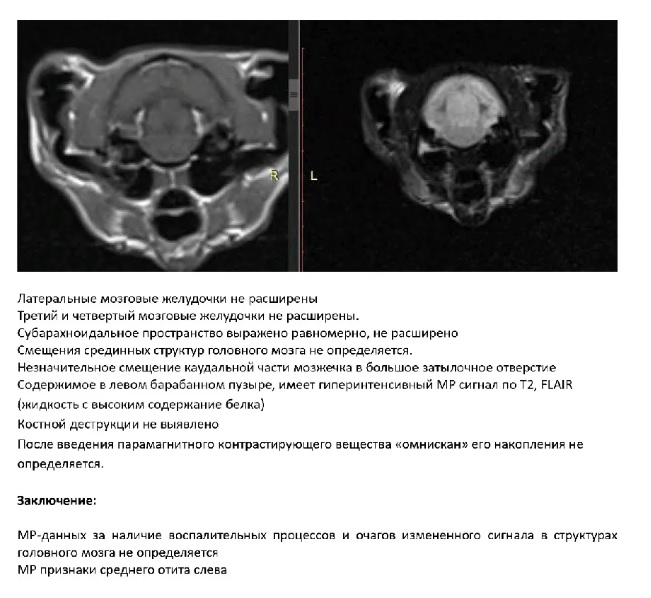

Отит среднего уха